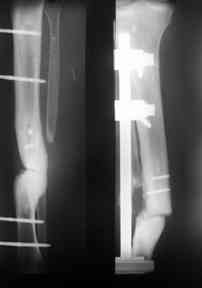

Больной 33 года поступил в отделене с открытой травмой голени на фоне тугого ложного сустава.

Первичная травма более десяти лет назад открытый перелом костей , перенес 8 операций по поводу несростающегося перелома голени и далее травматического остеомиелита и ложного сустава, Последние 2 года ходил с полной нагрузкой на конечность без ортопедического тутора, отмечал некоторую болезненность при значительных нагрузках. В результате падения получил травму голени, резкую потерю опороспособности, наличие раны по наружной поверхности голени в виде лучей 3х10х 4х8 см.Дном раны является кость. Кожа представляет из себя рубцы, которые "взорвались" при воздейстии на них отломков, вернее концов ложного сустава. Даже диагноз сложно сформулировать, скорее открытый ложный сустав 2-3типа. Первично срержневой аппарат,аддаптирующие швы на кожные лоскуты,сохраняется дефект кожи 4х6 см, да и на окружающие кожно -рубцовые ткани надежд нет, намечается некроз. Учитывая бесполезность сращения склерозированных концов ( а это доказано 10 летними попытками), а также значительный дефект кожи планируем произвести резекцию концов ( планируемый дефект 6-7 см), далее ЧКДО на укорочение, контатк отломков сращение с последующим восстновлением длинны за счет остетомии и транспорта в в/3 голени- это в стандарной ситуации. Есть идея совместить штифт и аппарат. Важны Ваши мнения и совет ув. коллеги!